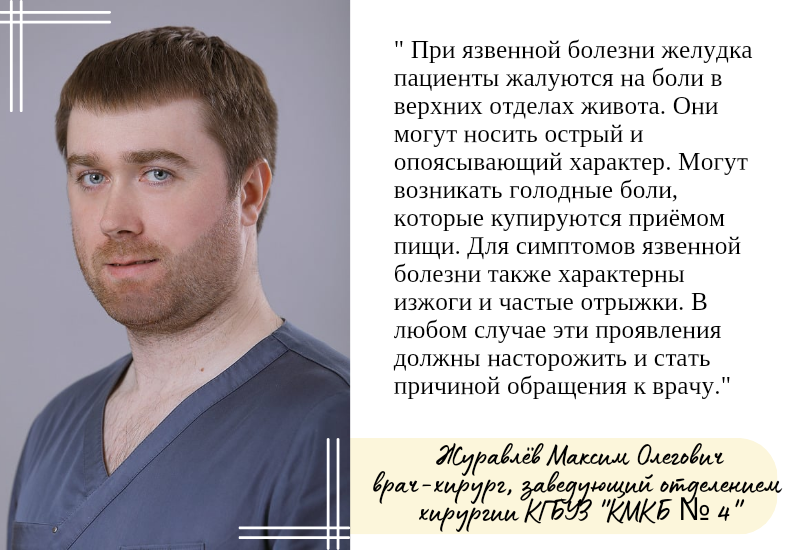

Рекомендации по питанию при язвенной болезни желудка

Язвенная болезнь желудка: факторы риска, симптомы и меры профилактики